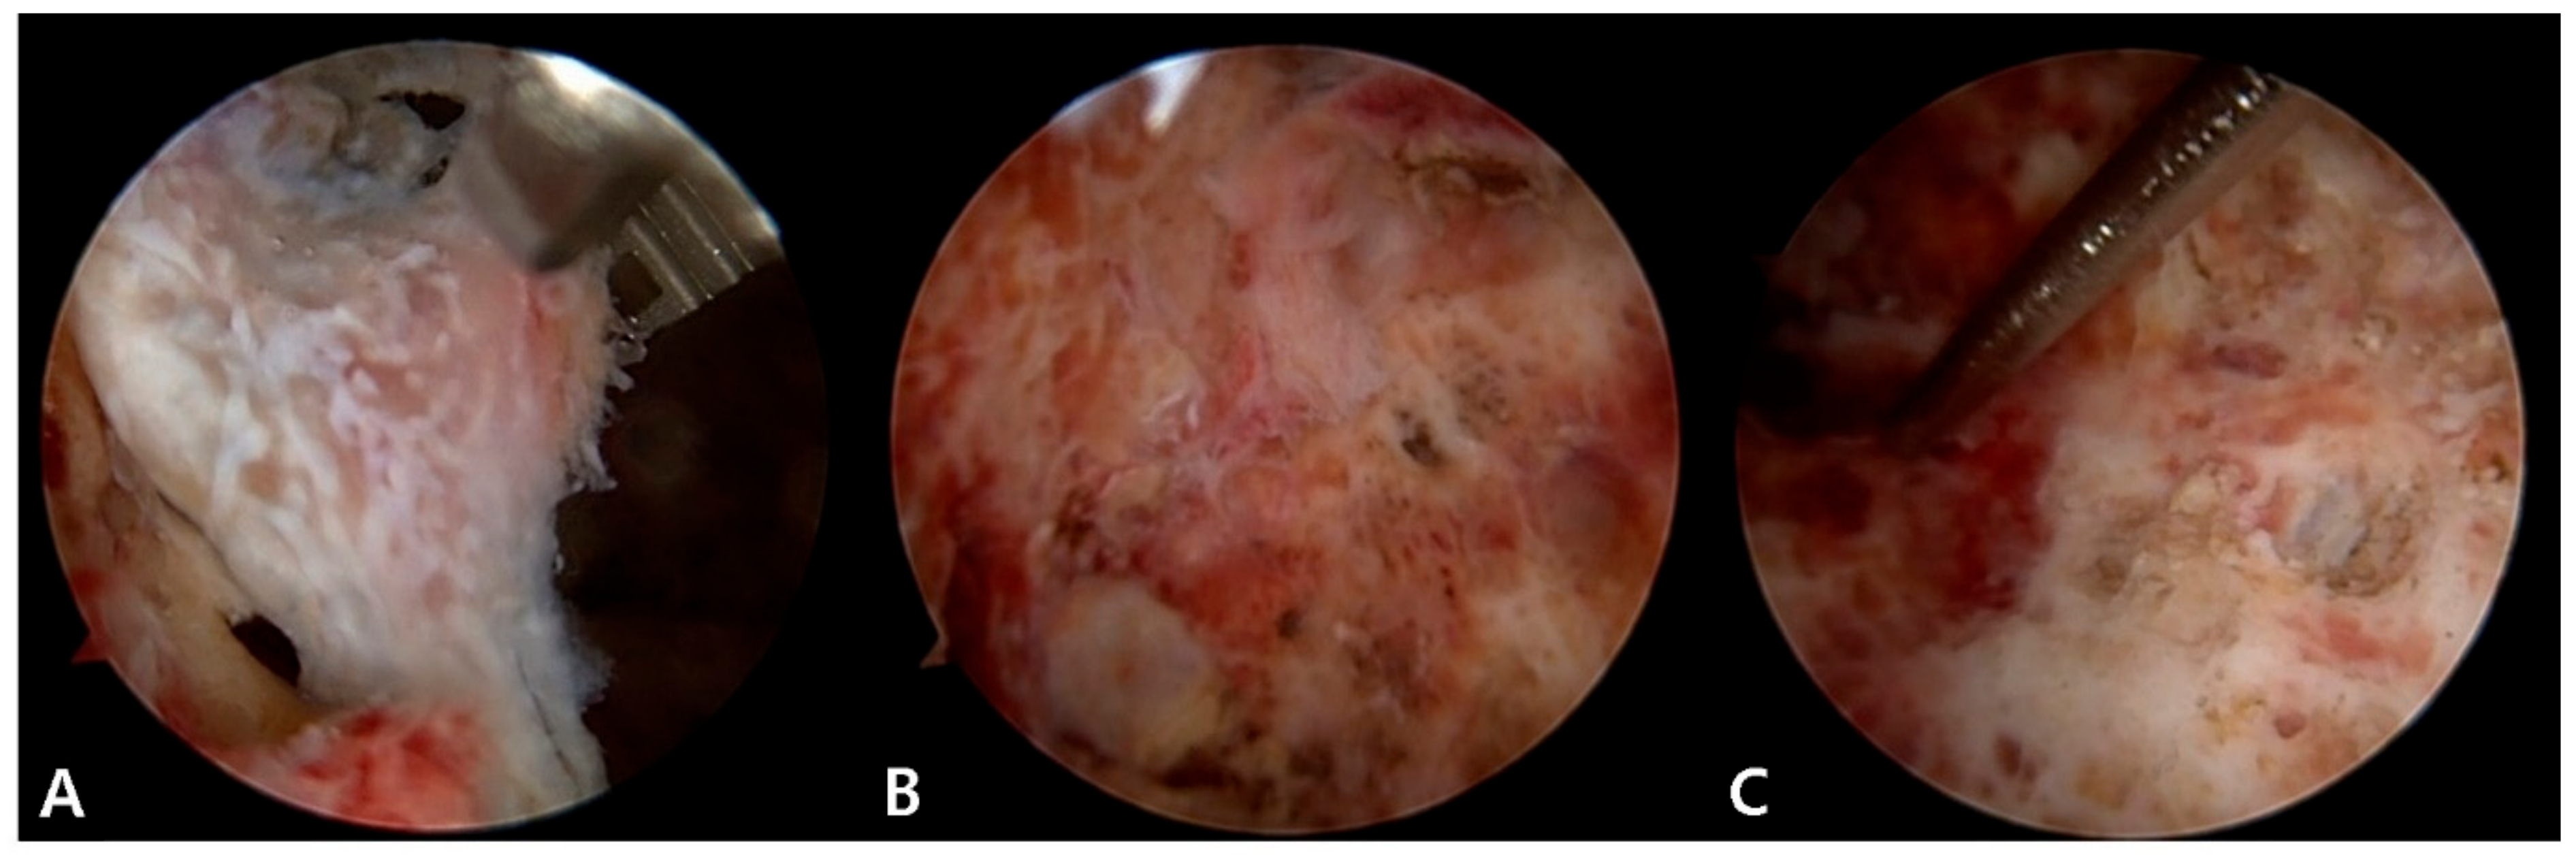

2.2. Surgical Procedure